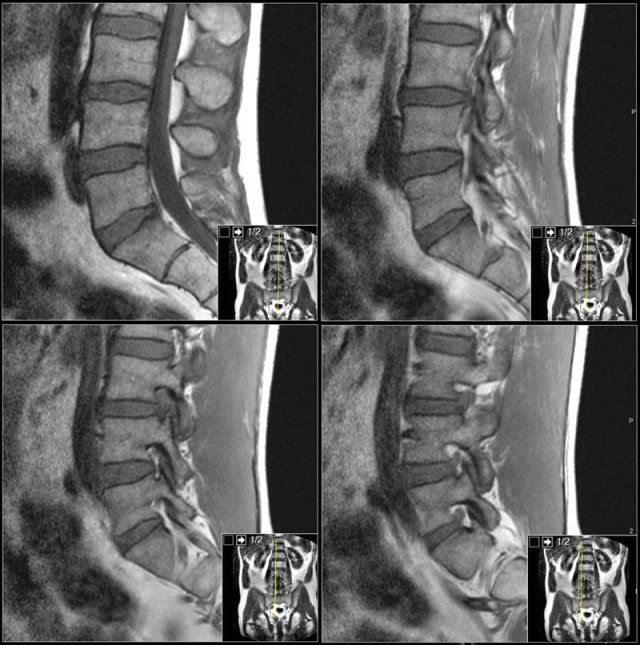

The MRI protocol for examination of the lumbar spine in patients with symptoms of nerve compression is quite simple.

Basically we rely on the sagittal T1W- and T2W-images and correlate the findings with the transverse T2W-images of the levels of suspected pathology.

It is better to have continuous slices with the same angulation parallel to the level where nerve compression is suspected.

This has the advantage, that you can follow the involved nerve along the four levels of possible compression.

When you examine multiple levels with different angulation like in the example on the right, you will not be able to follow the whole nerve tract and you will not get the whole picture.